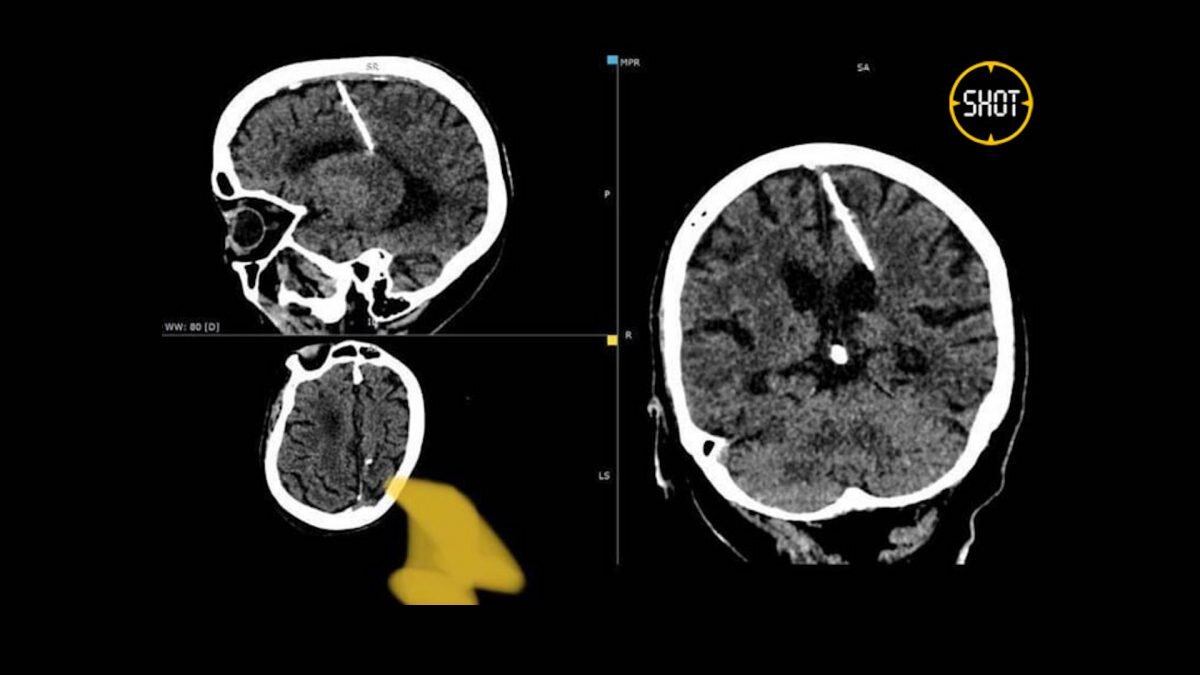

В мозге 80-летней жительницы Сахалина обнаружили трёхсантиметровую иглу, которая находилась там всю её жизнь. Иглу нашли случайно при проведении компьютерной томографии, и медики решили не доставать её, чтобы не навредить здоровью пациентки. Об этом сообщает Bizmedia.kz. 80-летняя жительница Сахалина жила всю жизнь с иглой в мозгу В мозге 80-летней жительницы сахалинского региона была обнаружена необычная находка — игла длиной в три сантиметра. По информации, размещенной в Telegram-канале Shot, женщина не была осведомлена о присутствии чужеродного объекта в течение всего своего века. Случайное открытие было сделано рентгенологами во время выполнения компьютерной томографии. «Считается, что родители женщины втащили иглу в ее голову при рождении во время военных трудностей, в надежде на ее гибель. Однако малышка пережила эту травму, и, что удивительно, никогда не жаловалась на головные боли», — говорится в сообщении. Врачи приняли решение не извлекать иглу из головы сахалинки, чтобы избе

В мозге 80-летней жительницы сахалинского региона была обнаружена необычная находка — игла длиной в три сантиметра. По информации, размещенной в Telegram-канале Shot, женщина не была осведомлена о присутствии чужеродного объекта в течение всего своего века.

Случайное открытие было сделано рентгенологами во время выполнения компьютерной томографии.